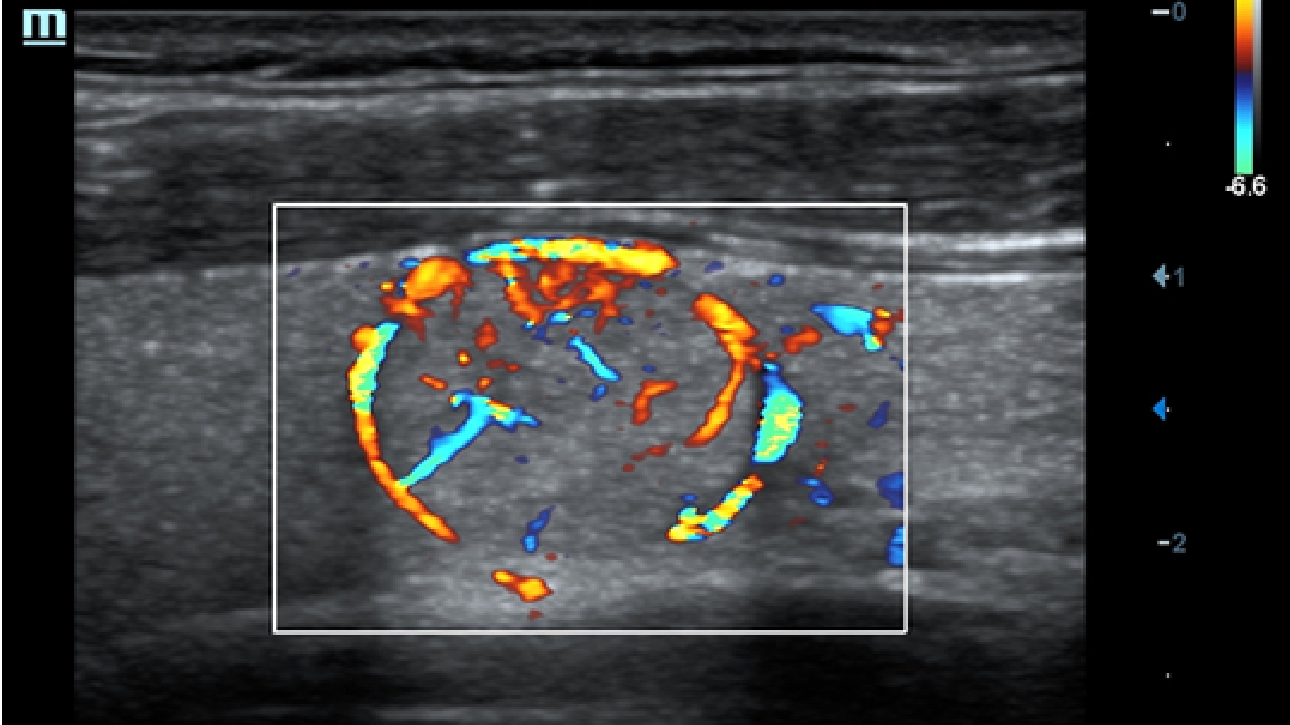

X-Insight ├© una soluzione completa studiata per offrire la migliore qualit├Ā diagnostica.

La nuova soluzione di Mindray ├© la traduzione pratica delle esigenze quotidiane dei clienti in soluzioni cliniche, il tutto con tecnologie ad ultrasuoni all'avanguardia ed in continua evoluzione.

Proponendosi come partner affidabile, DC-60 Exp con X-Insight si concentra su ci├▓ che conta veramente, semplificando la gestione della pratica clinica quotidiana con facilit├Ā e sicurezza.

Progettato per rispondere al meglio alle esigenze del cliente, DC-60 Exp con X-Insight ├© studiato per offrire un'efficienza elevata nel campo dell'imaging di precisione, grazie a una chiarezza immediata (eXpress Clarity), allŌĆÖeccezionale intelligenza (eXceptional Intelligence), oltre a vantare una lunghissima esperienza (eXceeding Experience).